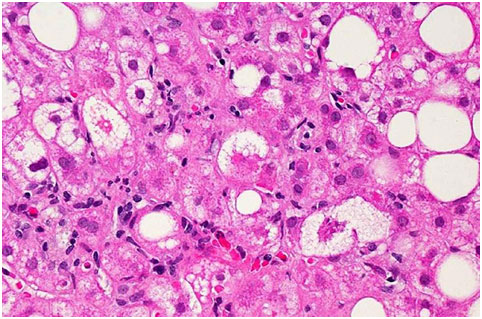

受非酒精性脂肪肝(NAFLD)影響的肝組織的顯微圖像。大白點(diǎn)和小白點(diǎn)是填充肝細(xì)胞的多余脂肪滴